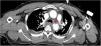

Varón de 49 años con traumatismo toracoabdominal cerrado tras colisión frontal por accidente de tráfico. En la body TAC se objetiva rotura de hemidiafragma derecho con herniación del lóbulo hepático derecho (asterisco) a la cavidad torácica, desplazamiento mediastínico y disección traumática de aorta descendente a la salida de la arteria subclavia izquierda (punta de flecha) en el plano coronal oblicuo (fig. 1) y transversal (fig. 2). Se realizó reducción quirúrgica urgente de la hernia diafragmática y aortografía diferida (fig. 3) con reparación aórtica mediante endoprótesis. La asociación de una rotura hemidiafragmática derecha y una disección aórtica traumáticas es muy inusual. Se asocia a mecanismos de alta energía-desaceleración, son potencialmente mortales y muertes evitables con un diagnóstico y tratamiento precoz.